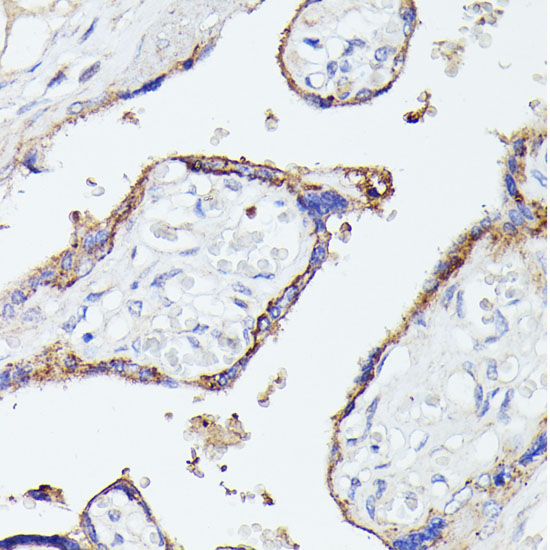

Immunohistochemistry of paraffin-embedded human placenta using LTF at dilution of 1:100 (40x lens).